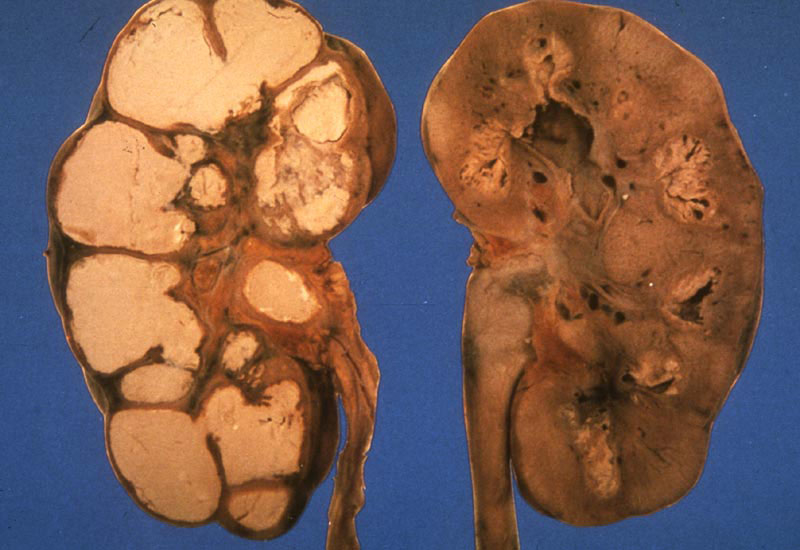

Согласно рентгенологической классификации, туберкулез почек делится на несколько форм и стадий:

| Форма туберкулезного процесса | Описание изменений |

| Туберкулез почечной паренхимы | Очаги поражения преимущественно располагаются в корковом веществе почки. На рентгенограммах наблюдаются деформации и неупорядоченное расположение чашечек |

| Туберкулезный папиллит | Это начальная стадия деструктивного туберкулеза. В области чашечек на верхушке пирамиды почки фиксируется разрушение |

| Кавернозная форма | Вокруг разрушенных чашечек образуются капсула и полость. Количество каверн может варьироваться от одной до нескольких |

| Фиброзно-кавернозная форма | Пораженные чашечки зарастают, образуя замкнутые полости, заполненные гноем |

| Туберкулезный пионефроз | Гнойные полости сливаются и распространяются по всему органу, что приводит к его полной разрушенности |

Чем более выражены деструктивные изменения в почечной ткани, тем более запущенной является стадия заболевания. Клинические проявления также напрямую зависят от степени повреждения органа и будут ухудшаться по мере его разрушения.